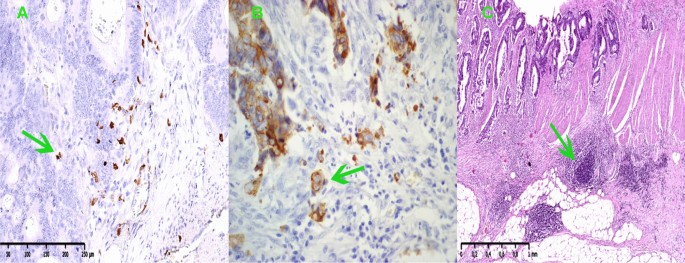

Tumor budding foci (TBFs) were defined as isolated cancer cells or clusters of ≤ 4 cells in the stroma at the invasive margin using H&E staining and cytokeratin immunohistochemical staining, Fig. 1B. The number of TBFs in the invasive frontal region was counted within the field of densest budding of 0.785 mm2 at 20 × magnification and graded according to its number as low (TBF-1): 0–4 buds, intermediate (TBF-2): 5–9 buds, and high-grade (TBF-3): ≥ 10 buds9. The invasive front is a 1-mm region centered on the border separating the malignant cell nests from the host tissue10. The tumor center represents the remaining tumor area inside the invasive front and the peritumor area corresponds to tissue outside of the invasive front. The invasive front of colorectal cancer represents a dynamic interface between pro- and antitumor factors11. The infiltrating tumor border configuration and tumor budding promote the progression and dissemination of tumor cells by penetrating the vascular and lymphatic vessels, and the host attempts to fend off this attack by mounting an immune response using cytotoxic T lymphocytes.

(A) Representative examples of CD8 cells expression in colorectal cancer tissue, × 100 magnification. (B) Representative examples of tumor budding at the front of invasion in colorectal cancer tissue, × 40 magnification. (C) Representative examples of lymphoid follicles in the front of tumor invasion in colorectal cancer tissue, × 40 magnification.

Tissue sections were stained by immunohistochemistry according to the XT-ultraView-DABv3 procedure. Tumor-infiltrating lymphocytes (TILs) and tumor-associated neutrophils (TANs) were assessed in tissue material stained with hematoxylin and eosin, and evaluated by a pathologist who was blinded to any patient clinical data, Fig. 1A. At the same time, the tissues were assessed for the presence of lymphoid follicles, Fig. 1C. To identify the types of lymphocytes, the following three antibodies were used: anti-CD3 (2GV6) rabbit monoclonal primary antibody (Ventana), anti-CD4 (SP35) rabbit monoclonal primary antibody (Ventana), anti-CD8 (SP57) rabbit monoclonal antibody (Ventana). Staining was performed automatically on the Benchmark XT using Ventana’s proprietary protocols. The histopathological assessment was performed using an Olympus CX21 light microscope at 400 × magnification. Tumor-infiltrating immune cells (TIICs) were detected in five randomly chosen, nonadjacent, nonoverlapping areas separately at the tumor center (TC) and at the invasive front (IF) to ensure uniformity and representativeness of the obtained results. Tumor-infiltrating immune cells were counted in 5 fields of view [FOV], the number of cells was calculated on 0.785 mm2 of the tissue surface, and the result was the mean value [cells/FOV].